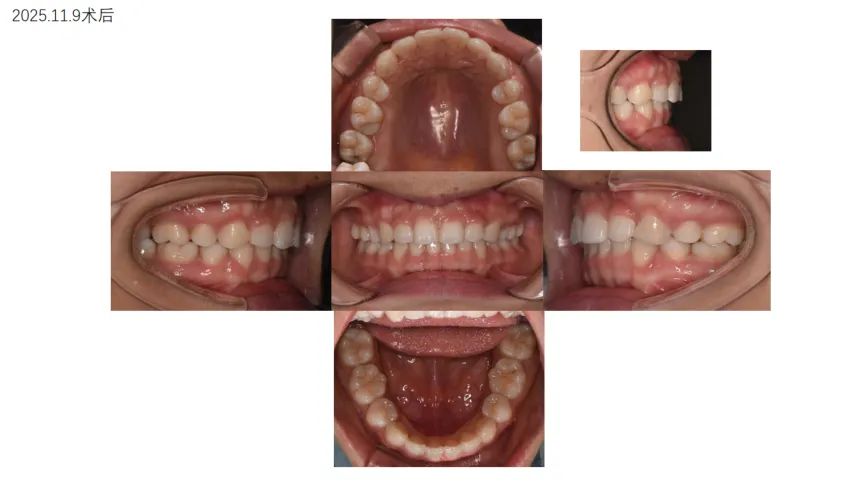

病例展示: